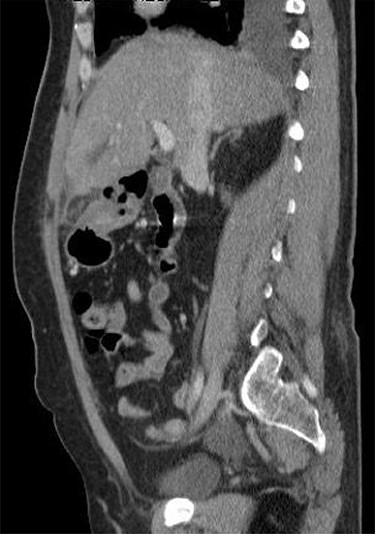

A 53-year-old fit and well woman presented to the emergency department with acute epigastric and right hypochondrium pain with a positive Murphy’s sign of the abdomen. The patient was anicteric and apyrexial. Blood tests performed revealed a white cell count of 13.6 × 109/L and a C-reactive protein of 110 U/L. Liver function tests, amylase and urea and electrolytes were unremarkable. A working diagnosis of acute cholecystitis was made and the patient commenced on intravenous fluids and intravenous antibiotics. Abdominal ultrasound was performed, which demonstrated no gallstones nor choledocholithiasis and was essentially normal. Given the raised inflammatory markers and persistent abdominal pain, CT scan was performed (Fig. 1). This revealed a 32 × 22-mm oval-shaped fat density lesion with peripheral hyper attenuation adjacent to the falciform ligament, representing intraperitoneal focal fat infarction of the fatty appendage of falciform ligament. Sagittal reconstruction showed a central hyperdense thrombosed vessel secondary to torsion of the falciform ligament (Fig. 2).

Contrast-enhanced CT scan shows a 32 × 22-mm oval-shaped fat density lesion with peripheral hyperattenuation and central hyperdense dot adjacent to falciform ligament. There is surrounding oedema and inflammation. Gall bladder is noted to be unremarkable. Features represent intraperitoneal focal fat infarction of fatty appendage of falciform ligament.